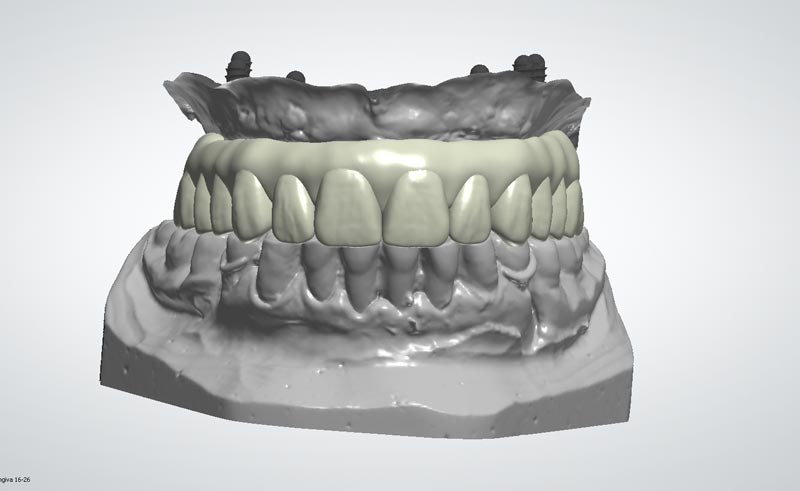

Modellazione protesica